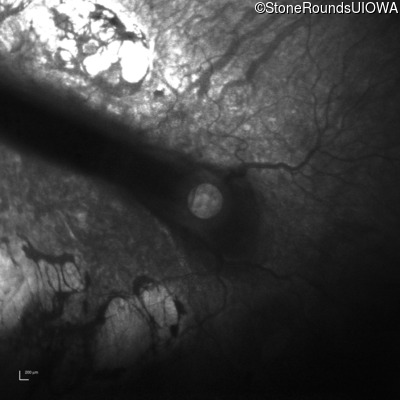

Infrared Fundus Photograph - Right - 20/500

Exemplar

Infrared Fundus Photograph - Left - 20/300